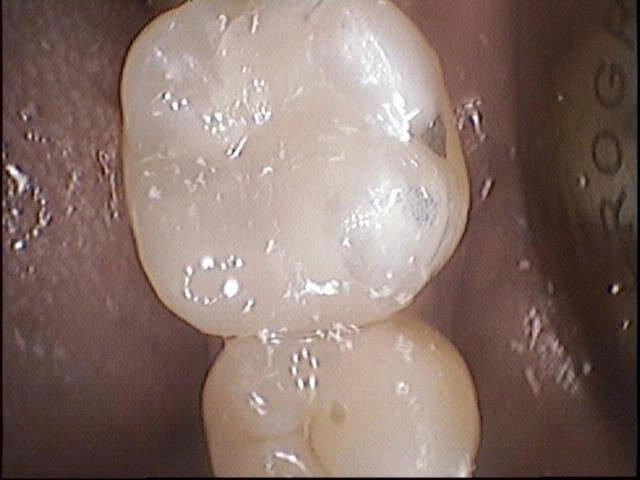

Dental fillings are necessary to repair decayed or broken tooth structure in order to prevent sensitivity, food impaction, damage to tongue and oral tissues from sharp edges of the teeth, and toothaches. We use modern dental filling materials such as tooth coloured composite resin, glass-ionomer cements, and porcelain. Amalgam fillings are no longer used routinely but is still available if necessary. We offer amalgam replacement options as well and this should be discussed with our dentists first prior to commencing.